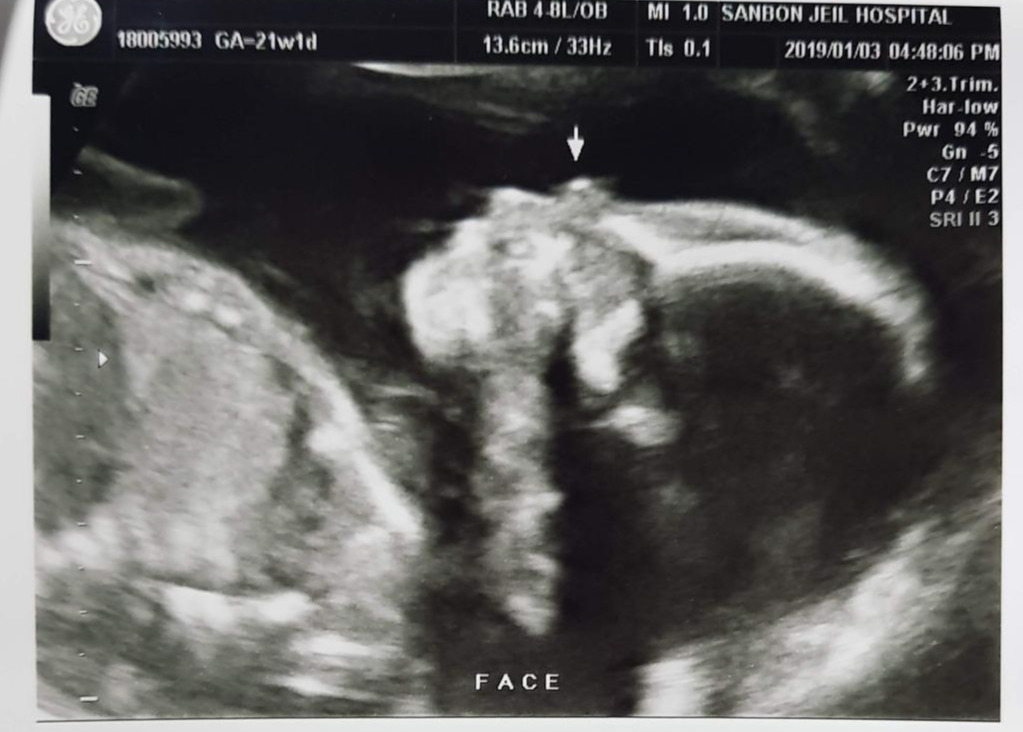

20190103_171801.jpg

짠짠이 21주 차

21주.

기형아 검사에 마음 졸인 엄마 아빠와는 상관없이 짠짠이는 한껏 자라서 이제 아기집이 좁다. 이사도 하고 새해를 맞이하여 새로운 환경에서 잘 자라는 중. 아내는 이제 누가 보기에도 임산부 티가 난다. 좁아진 엄마 뱃속에서 열심히 뒹구느라 배를 슬슬 차기 시작했다. 이 즈음 아내는 첫 태동을 느끼고 짠짠이가 마음에 더 훅 들어와 버렸다고. 초반에는 태동이 오면 나에게도 느끼게 해 주려고 애를 썼는데 나중에는 시시때때로 짠짠이 발길질을 느끼게 되었다. 낮은 음성의 아빠 목소리가 좋다고 하여 아내 배를 만지면서 종종 태담을 하던 시기. 태담이라고 해봤자 "어~ 음~ 오~ 우~ 아~" 이런 갖가지 의성어를 들려주는 정도였는데, 아내는 어른의 말을 하라고 성화였다. 그래서 가끔 태교동화도 읽어주고. 그런데 나는 왠지 짠짠이와 짠짠이 언어로 대화를 하고 싶었다. 물론 그 의성어들이 짠짠이 언어인지는 확인할 길이 없지만. 어른 말은 엄마가 해줄 테니 나는 짠짠이 말로! 뭐 이런 이상한 고집.